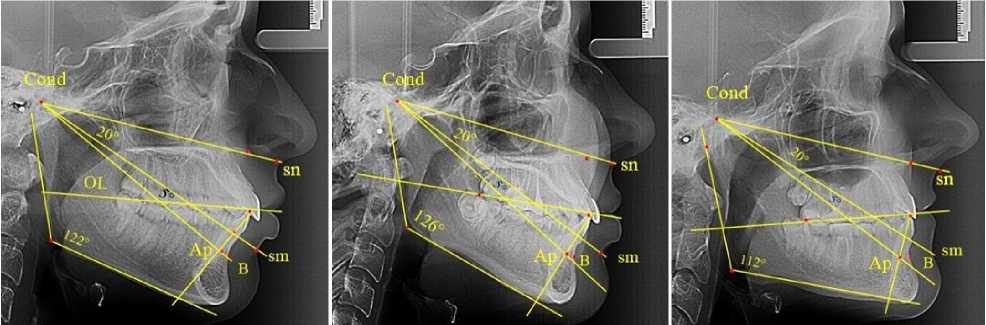

Среди людей с физиологической окклюзией на 15 рентгенограммах из 32 [(46,87 ± 8,82) %] был выявлен нейтральный тип роста, и величина нижнечелюстного угла варьировала в пределах 118–123°. В 7 случаях [(21,87 ± 7,31) %] определялся вертикальный тип роста с величиной угла нижней челюсти более 124°. На 10 телерентгенограммах угол нижней челюсти был менее 117° (горизонтальный тип), что составило (31,25 ± 8,19) % от числа людей с физиологической окклюзией. Результаты анализа рентгенограмм представлены на рис. 3.

а                                  б                                 в

Рис. 3. Особенности ТРГ при нейтральном (а) вертикальном (б) и горизонтальном (в) типах роста нижней челюсти

Результаты исследования показали, что при нейтральном типе роста угол гнатической части лица составлял (19,93 ± 0,48)°. На рентгенограммах с вертикальным типом роста ниж- ней челюсти анализируемый угол был (20,07 ± 0,56)°, а при горизонтальном типе – (20,01 ± 0,36)°. Таким образом, угол гнатической части лица составлял в среднем 20°, вне зависимости от типов роста нижней челюсти, что может быть использовано при анализе аномалий окклюзии в вертикальном направлении.

Величина апикально-кондилярного угла в 5° определяла положение апикальной точки ( Ар ) при пересечении апикально-кондилярной линии с условной срединной вертикалью нижнего резца. Определение точки апикального базиса по Schwarz ( В ) на контуре передней поверхности нижней челюсти проводили с учетом равенства расстояний IsL-Ap = IsL-B .

Таким образом, при физиологической окклюзии вне зависимости от типологических особенностей нижнечелюстного угла величина назально-суставного угла (sn-Cond-sm) в пределах 20° определяла оптимальную высоту прикуса и вертикальные размеры переднего отдела гнатической части лица. В то же время угол sm-Cond-Ар в пределах 5° позволял его использовать в качестве ориентира апикальной точки нижнего медиального резца на боковых ТРГ вне зависимости от наложения рядом расположенных рентгеноконтрастных структур.